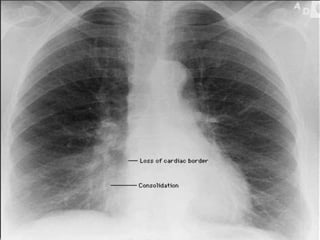

Bulging Fissure Sign

The bulging fissure sign refers to lobar consolidation where the affected

portion of the lung is expanded.

It is now rarely seen due to the widespread use of antibiotics.

Bulging Fissure Sign Thebulging fissure sign refers to lobar consolidation where the affected portion of the lung is expanded. It is now rarely seen due to the widespread use of antibiotics.